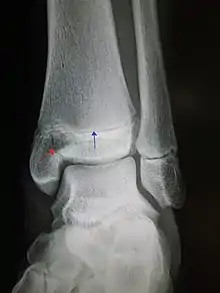

An X-ray of the left ankle showing a Salter–Harris type III fracture of medial malleolus. Red arrow demonstrates fracture line while the blue arrow marks the growth plate. | |